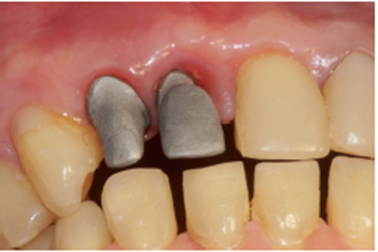

No laboratório, o técnico de prótese posicionou o pilar Ideale angulado no modelo (Figura 27) e confeccionou um incisivo central parafusado sobre ele, utilizando a coifa de provisório que o sistema oferece (Figura 28). Uma vez obtido o provisório, o cicatrizador voltou a ser removido e o pilar Ideale e o provisório foram instalados em boca (Figuras 30 e 31). O pilar foi torqueado em 20 Ncm e o parafuso da coroa foi torqueado em 10 Ncm. Após 15 dias, o provisório foi removido e observou-se o perfeito perfil de emergência que havia sido obtido (Figura 33). Neste novo momento foi posicionado sobre o pilar um transferente plástico de moldeira fechada do pilar Ideale, sendo que tanto o pilar como o dente 12 foram moldados (Figura 34) para a confecção de copings e posterior a aplicação da cerâmica (Figura 35).

Após a conclusão desses passos pelo laboratório, a prótese do elemento 12 foi cimentada com fosfato de zinco e a prótese sobre o pilar Ideale foi parafusada e torqueada a 10 Ncm (Figura 36). O orifício de acesso foi restaurado com resina fotopolimerizável (Figura 37). Uma radiografia final foi realizada, demonstrando o perfeito assentamento da coroa sobre o pilar Ideale.